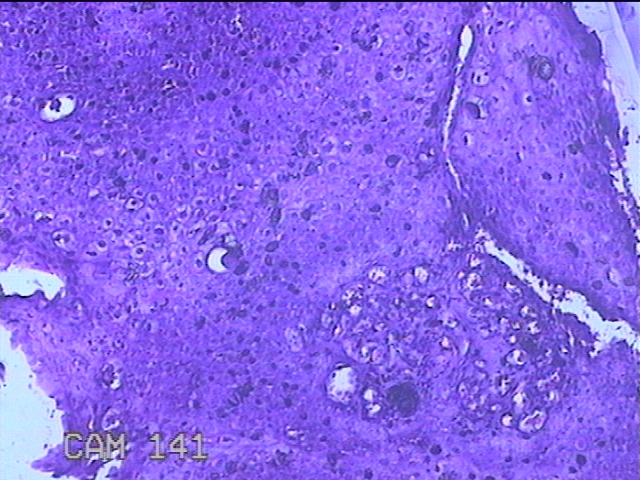

尿道口肿物

性别

男

年龄

46岁

临床诊断

尿道肿物

一般病史

发现尿道口肿物10余天。

标本名称

大体所见

灰白粉红色不规则肿物0.8x0.5x0.2一堆。

似有挖空细胞,有可能要考虑湿疣,片子这个效果,真是不敢猜。